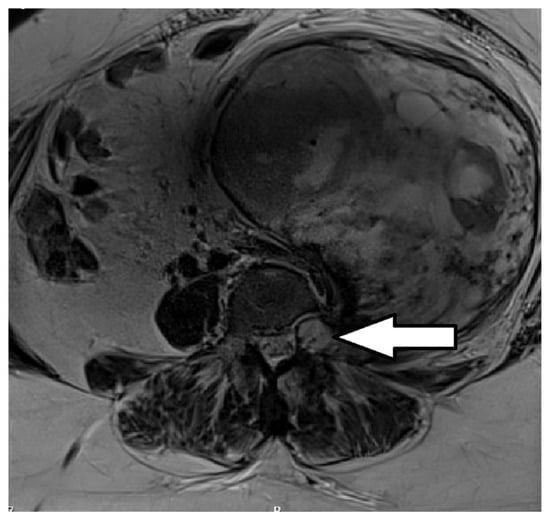

A Rare Case of a Gigantic Retroperitoneal Schwannoma

2. Case Report